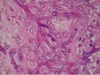

A

- bacterial endocarditis

- little irregular blue things = inflammatory cells

- bottom right corner = fibrin

- smudgy blue material = masses of bacteria